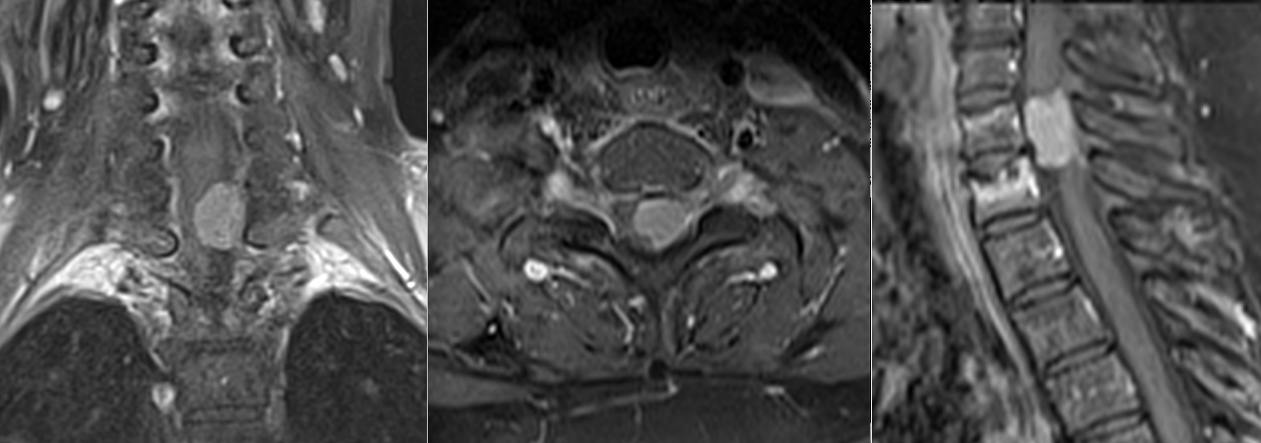

Schwannom radicular C5 stânga

Meningiom spinal cervical C7-T1 – RMN preoperator

Meningiom spinal cervical C7-T1 – RMN postoperator